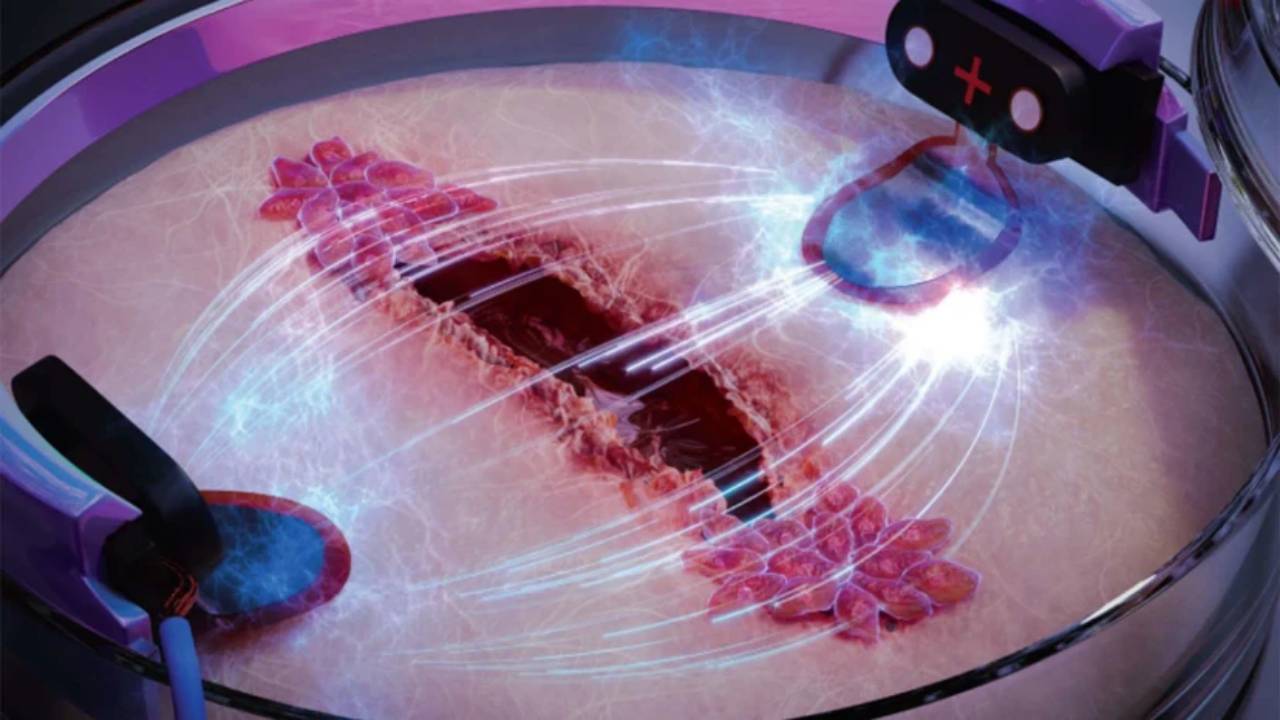

En un giro inesperado, investigadores han desarrollado una estrategia revolucionaria para inmunizar a las personas utilizando mosquitos portadores de parásitos genéticamente modificados. Esta técnica, aunque controvertida, ha demostrado ser sorprendentemente efectiva en ensayos iniciales, abriendo una puerta a nuevas posibilidades en la lucha contra esta enfermedad devastadora.

La investigación, publicada en The New England Journal of Medicine, propone una solución poco convencional: convertir a los mosquitos en aliados en lugar de enemigos. Los científicos infectaron mosquitos con una versión modificada genéticamente del Plasmodium falciparum, el parásito responsable de la malaria. Estos parásitos alterados están diseñados para provocar una respuesta inmunitaria en los humanos sin causar la enfermedad.